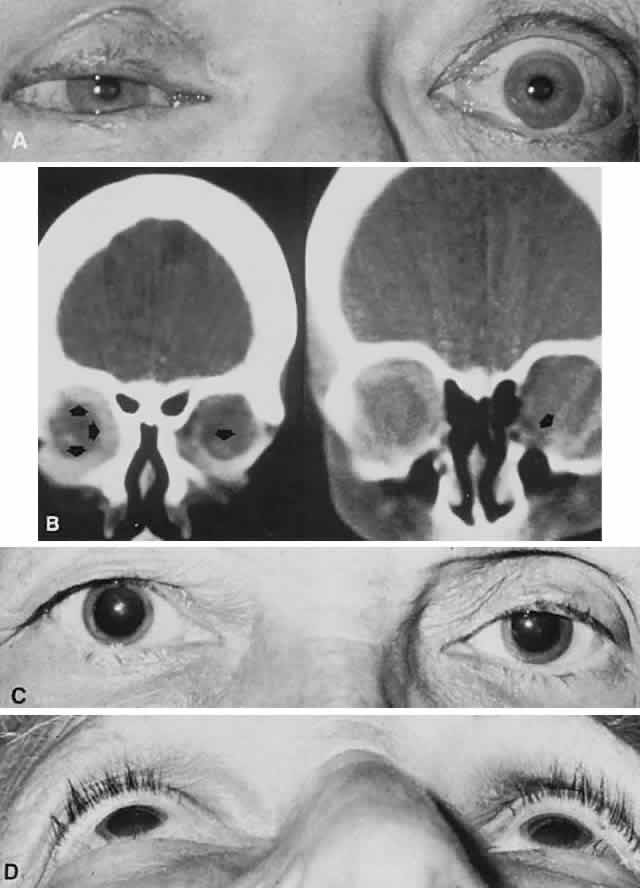

The clinician should be aware of several situations in which proptosis is more apparent than real, that is, a condition of pseudo-exophthalmos: unilateral lid retraction, wherein the homolateral eye appears larger; unilateral mild ptosis, wherein the contralateral eye appears larger; asymmetry of facial bones including orbital rims; and unilateral enophthalmos,17 wherein the normal contralateral eye appears prominent (Fig. 9). The differential diagnosis of enophthalmos is included in Table 3.

Fig. 9. Enophthalmos. A. A 56-year-old woman with right enophthalmos and fixation of the globe, and proptosis of the left eye. B. Bilateral orbital metastases of scirrhous breast carcinoma were disclosed by CT scan. C. Patient was referred for right proptosis but actually had left enophthalmos caused by simple senile atrophy of orbital fat pad, without history of facial trauma; note sunken superior lid sulcus on left (C), and relative position of left globe and lids, as viewed from below (D).